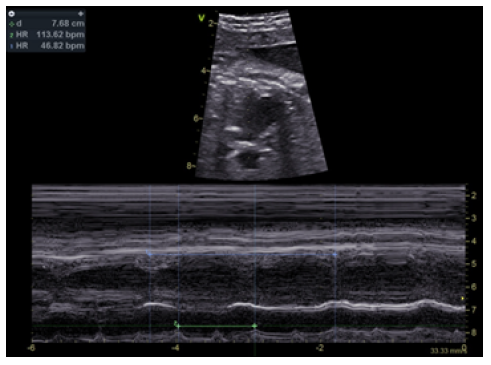

The degree of AV block can be categorized as first-degree, second-degree, or third-degree (complete) block.19 Fetuses with first-degree AV block have a prolongation of AV time (defined as a prolonged PR interval of >200 milliseconds), with 1:1 AV conduction and normal heart rate. Second-degree AV block is defined as failure of conduction of at least one nonpremature atrial impulse to the ventricles. Mobitz type I, or Wenckebach, is the most common type of second-degree AV block and usually involves progressive prolongation of the PR interval until an eventual failure to conduct an atrial beat to the ventricle. A second form of second-degree AV block, or Mobitz type II, is characterized by a constant PP interval without lengthening of the PR interval prior to the nonconducted P. In complete or third-degree AV block, the atrium and ventricle beat independently as a consequence of complete loss of the AV connection (Figures 1 and 2).19 AV block in NLE is usually complete at the time of diagnosis, but first- and second-degree block can also occur and may completely resolve during the first few months after birth.3 However, its severity may also change over time, developing into permanent complete heart block.2,3,5,13 Less frequently, damage to the conduction tissue may lead to transient sinus bradycardia, sinoatrial node dysfunction, prolongation of the QT interval, and Wolf-Parkinson-White syndrome.3 The clinical features of neonates with CHB depend on the effect of heart rate on cardiac output. Low heart rate may result in fetal or neonatal heart failure. Fetal hydrops and intrauterine death may occur in most severe cases. Postnatally, the typical signs of heart failure and low cardiac output manifest in neonates with poor hemodynamic status.2 Some neonates with complete AV block can develop compensatory mechanisms, although most require pacemaker implantation.2 Although NLE cardiac manifestations typically occur in utero or in the neonatal period, Rumancik et al. reported a case of “late-onset” neonatal lupus on a four-week-old girl presenting with severe dilated cardiomyopathy, dyskinetic ventricular septum, and left bundle branch block, highlighting the need for long-term cardiac follow-up of patients born with neonatal lupus, even if cardiac manifestations are lacking in the peripartum period.7 This case highlights the need for long- term cardiac follow-up of patients born with neonatal lupus, even if cardiac manifestations are lacking in the peripartum period.

Figure 2 Fetal echocardiogram showing complete atrioventricular block, with auricular rate of 113 bpm and ventricular rate of 46 bpm